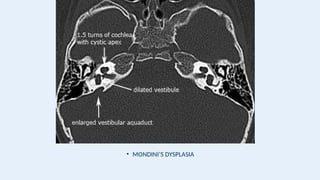

• High-resolution CT scanning, however, permits more complete characterization of hypoplasia,

aplasia, and incomplete partitioning defects (eg, the Modini deformity).

• MONDINI’S DYSPLASIA

• MRI hasbecome the diagnostic modality of choice for the detection of postmeningitic endocochlear obstruction. • Magnetic resonance imaging can demonstrate an absent or hypoplastic cochlear nerve. • Defects in the cribriform area of the cochlea, which present the likelihood of an intraoperative “gusher,” can be identified on MRI scanning and warn the surgeon about this potential difficulty. • High-resolution CT scanning, however, permits more complete characterization of hypoplasia, aplasia, and incomplete partitioning defects (eg, the Modini deformity).